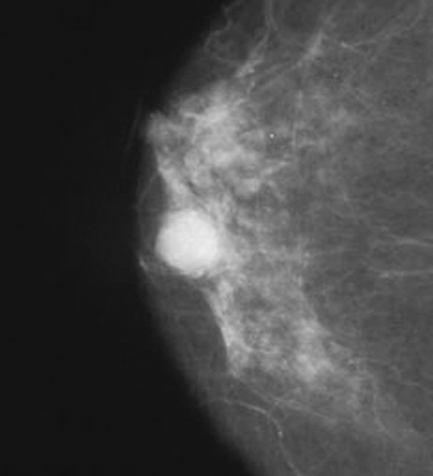

Radiology description

- Mammographically often presents as a spiculated mass with or without calcifications but may present as an architectural distortion or calcifications alone

- Targeted ultrasonography often used to enhance visualization

- MRI often shows enhancing mass lesion with variable washout kinetic patterns (Breast J 2010;16:394)

- MRI is sensitive but nonspecific technique is reserved for screening patients at high risk (e.g., BRCA mutation carriers), patients with dense breast tissue, estimating extent of disease in patients with lobular carcinoma, evaluating response to neoadjuvant chemotherapy or evaluating indeterminate abnormalities on mammography / ultrasound (Breast 2013;22:S77)